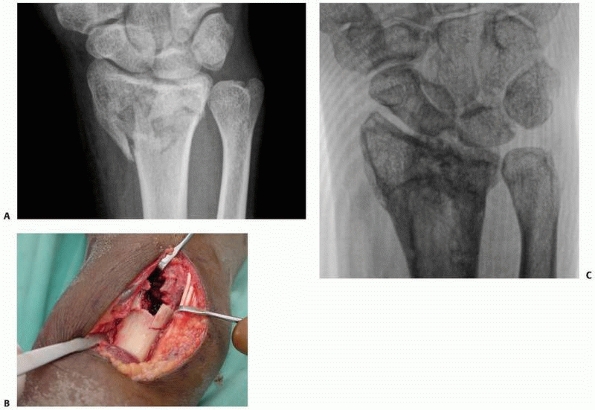

![]() |

FIGURE 30-8

The cross-sectional anatomy of the radius with comminution dorsally and radially. Note the tendency to dorsal collapse is the result of dorsal comminution and the collapse at the midcarpal joint. |

FIGURE 30-11 A. Disruption of the critical corner of the radius results in depression of the lunate facet. B-E. The radiographic and clinical effects are demonstrated.

|